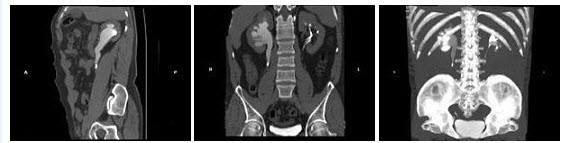

72、多项选择题

男,45岁,间断性腰背痛4个月,突发左下肢全肢水肿,小腿有张力性水泡,胸腹部CT扫描如图,下列哪些征象或结论正确()

A.下腔静脉缺如

B.下腔静脉变细

C.奇静脉增粗

D.奇静脉变细

E.正常CT表现